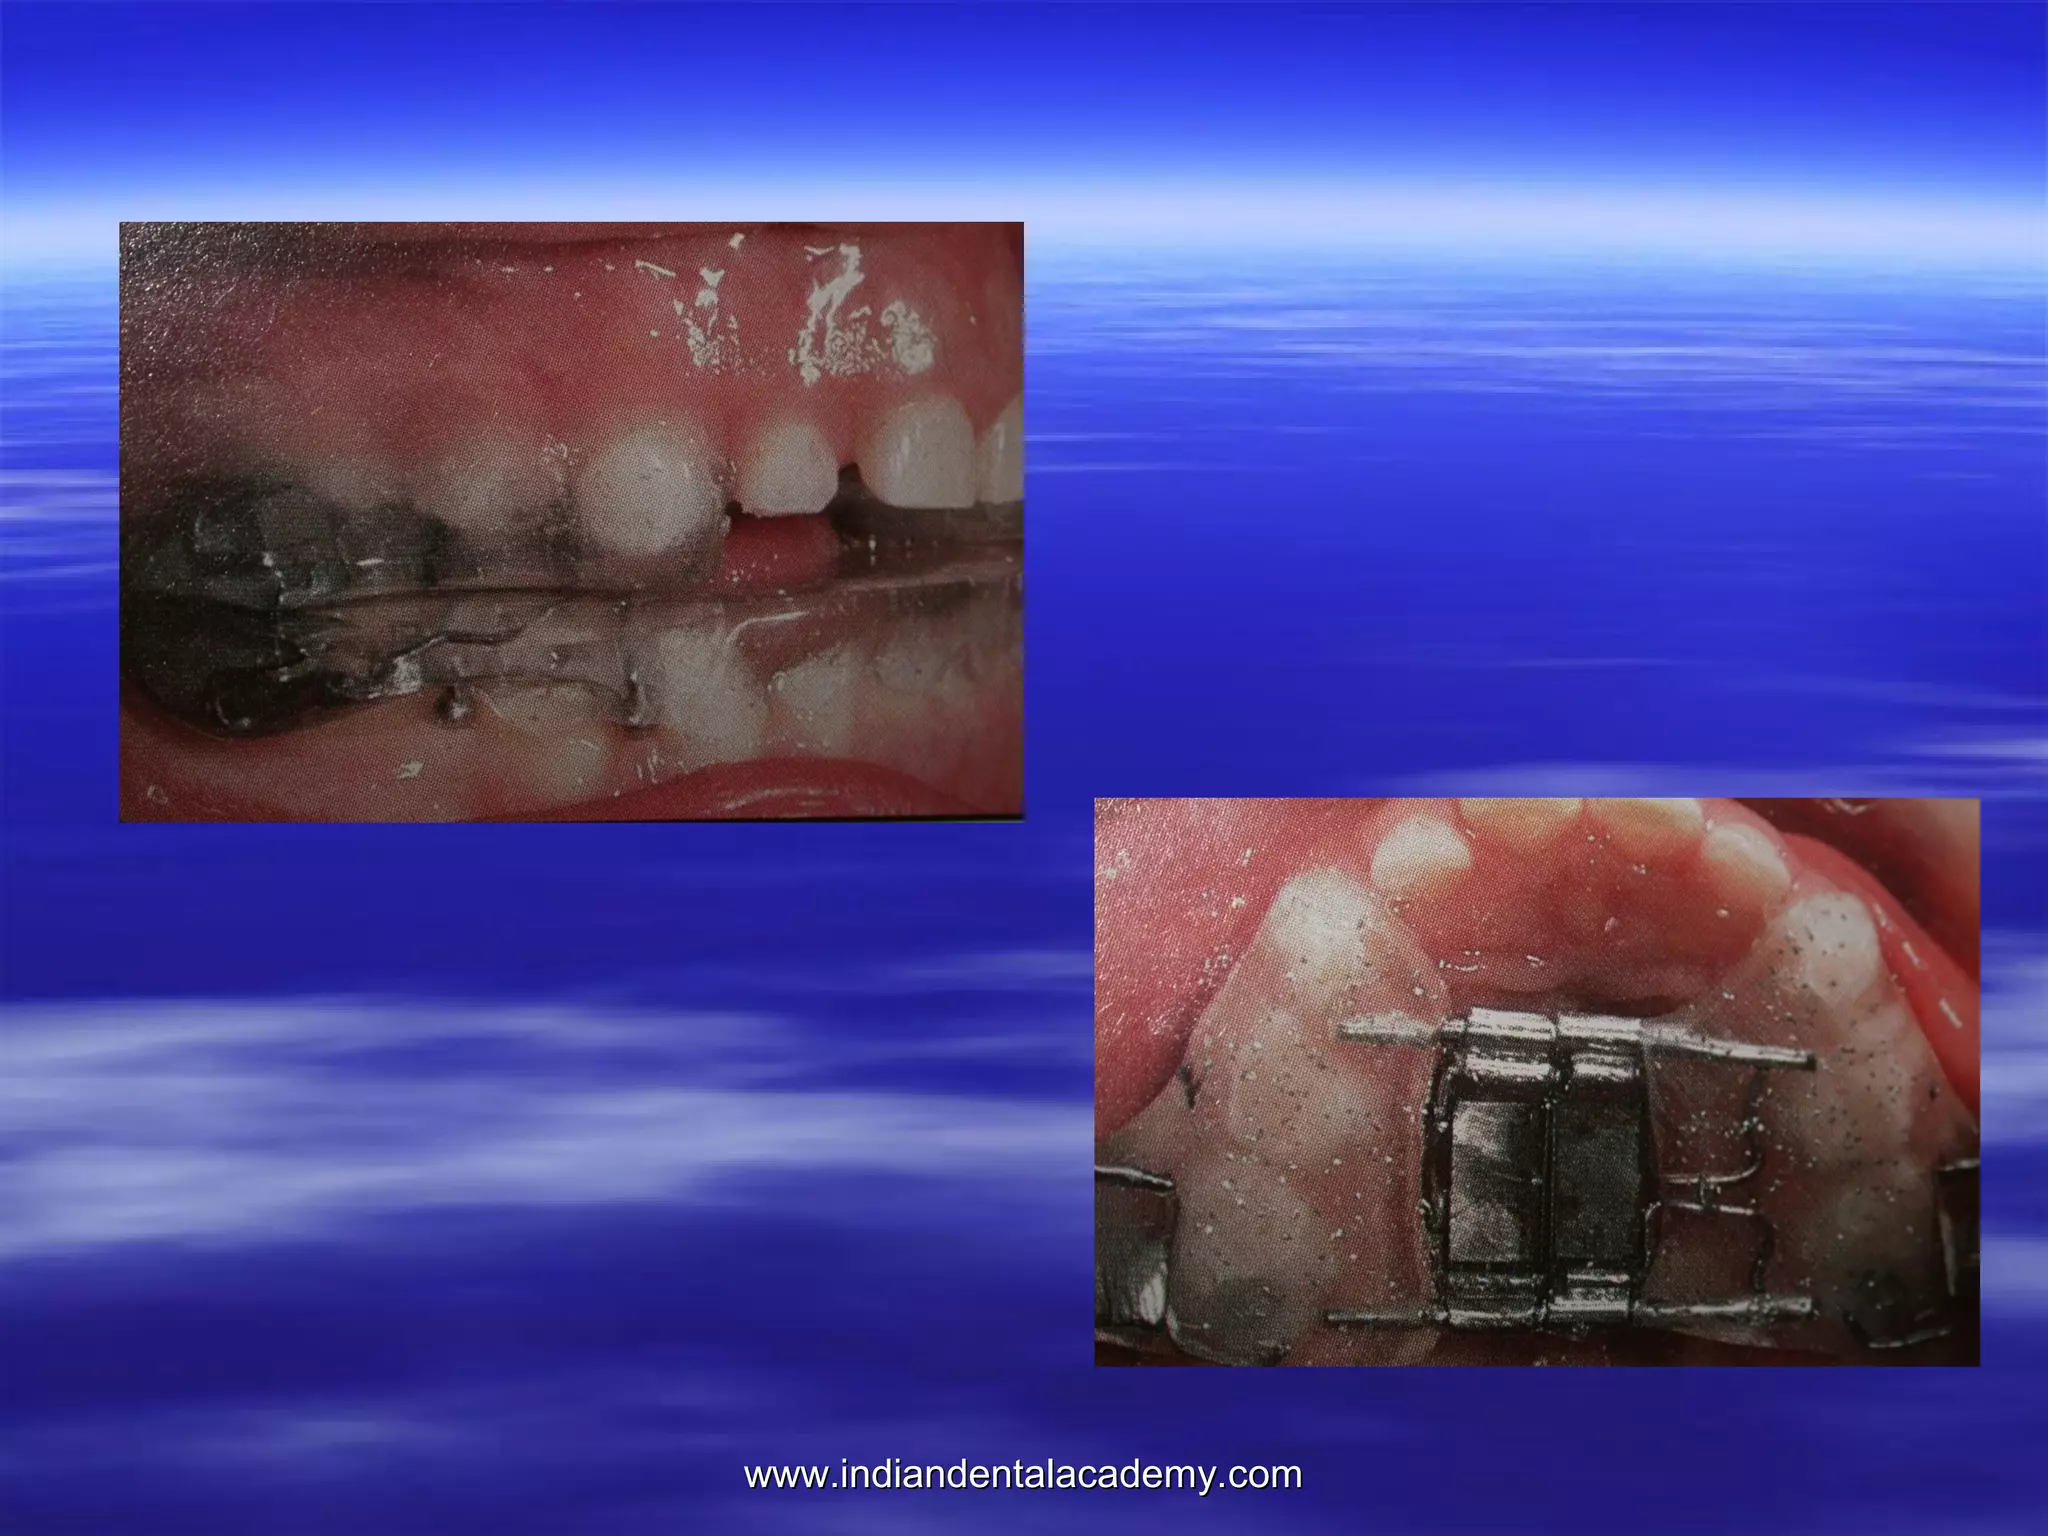

 Magnetic Activator Device(MAD):-Darendilier (1993) developed this magnetically active

MAD I-mandibular deviations

MAD II-CLII malocclusion

MADIII-CLIII malocclusion

MADIV-skeletal open bite correction.

MAD-II

MAD-II FOR CORRECTION OF CL-II,DIVISION 1

MALOCCLUSION.

Deep Bite

open Bite

 MAD III

www.indiandentalacademy.com